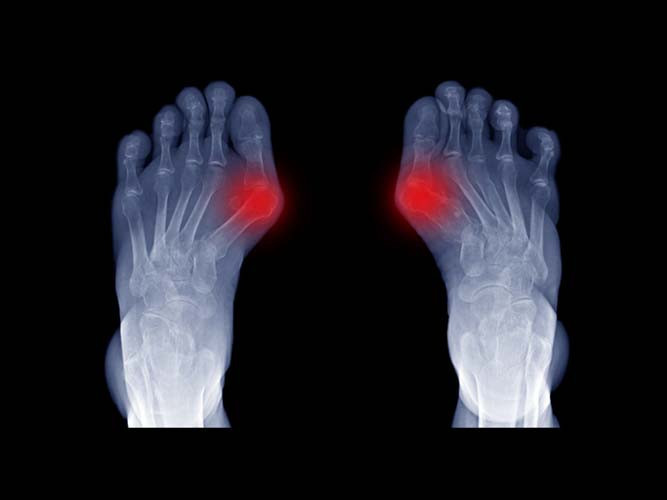

Halluks Valgus, ayak başparmağının diğer parmaklara doğru eğilmesi ve başparmağın altındaki tarak kemiğinin de ters yönde çıkıntı yapması ile kendini göstermektedir. Başparmağın eğiklik hastalığı olarak da bilinen Halluks Valgus kadınlarda daha sık görülmektedir.

Hastalarda sık görülen ve en çok şikayet konusu olan belirti, ayak baş parmağının kök kısmındaki çıkıntının ayakkabıya sürtünmesi ve ona bağlı olarak gelişen ağrı ile şişliktir. Sürtme sonucunda şişlik artmakta, şişlik arttıkça daha çok sürtünme olmaktadır. Sürtünmenin gerçekleştiği noktada bunyon adı verilen, kemiğin üzerinde büyük bir şişlik ile nasır oluşmaktadır. Devam eden bu kısır döngü, hastanın şikayetlerini artırmaktadır.